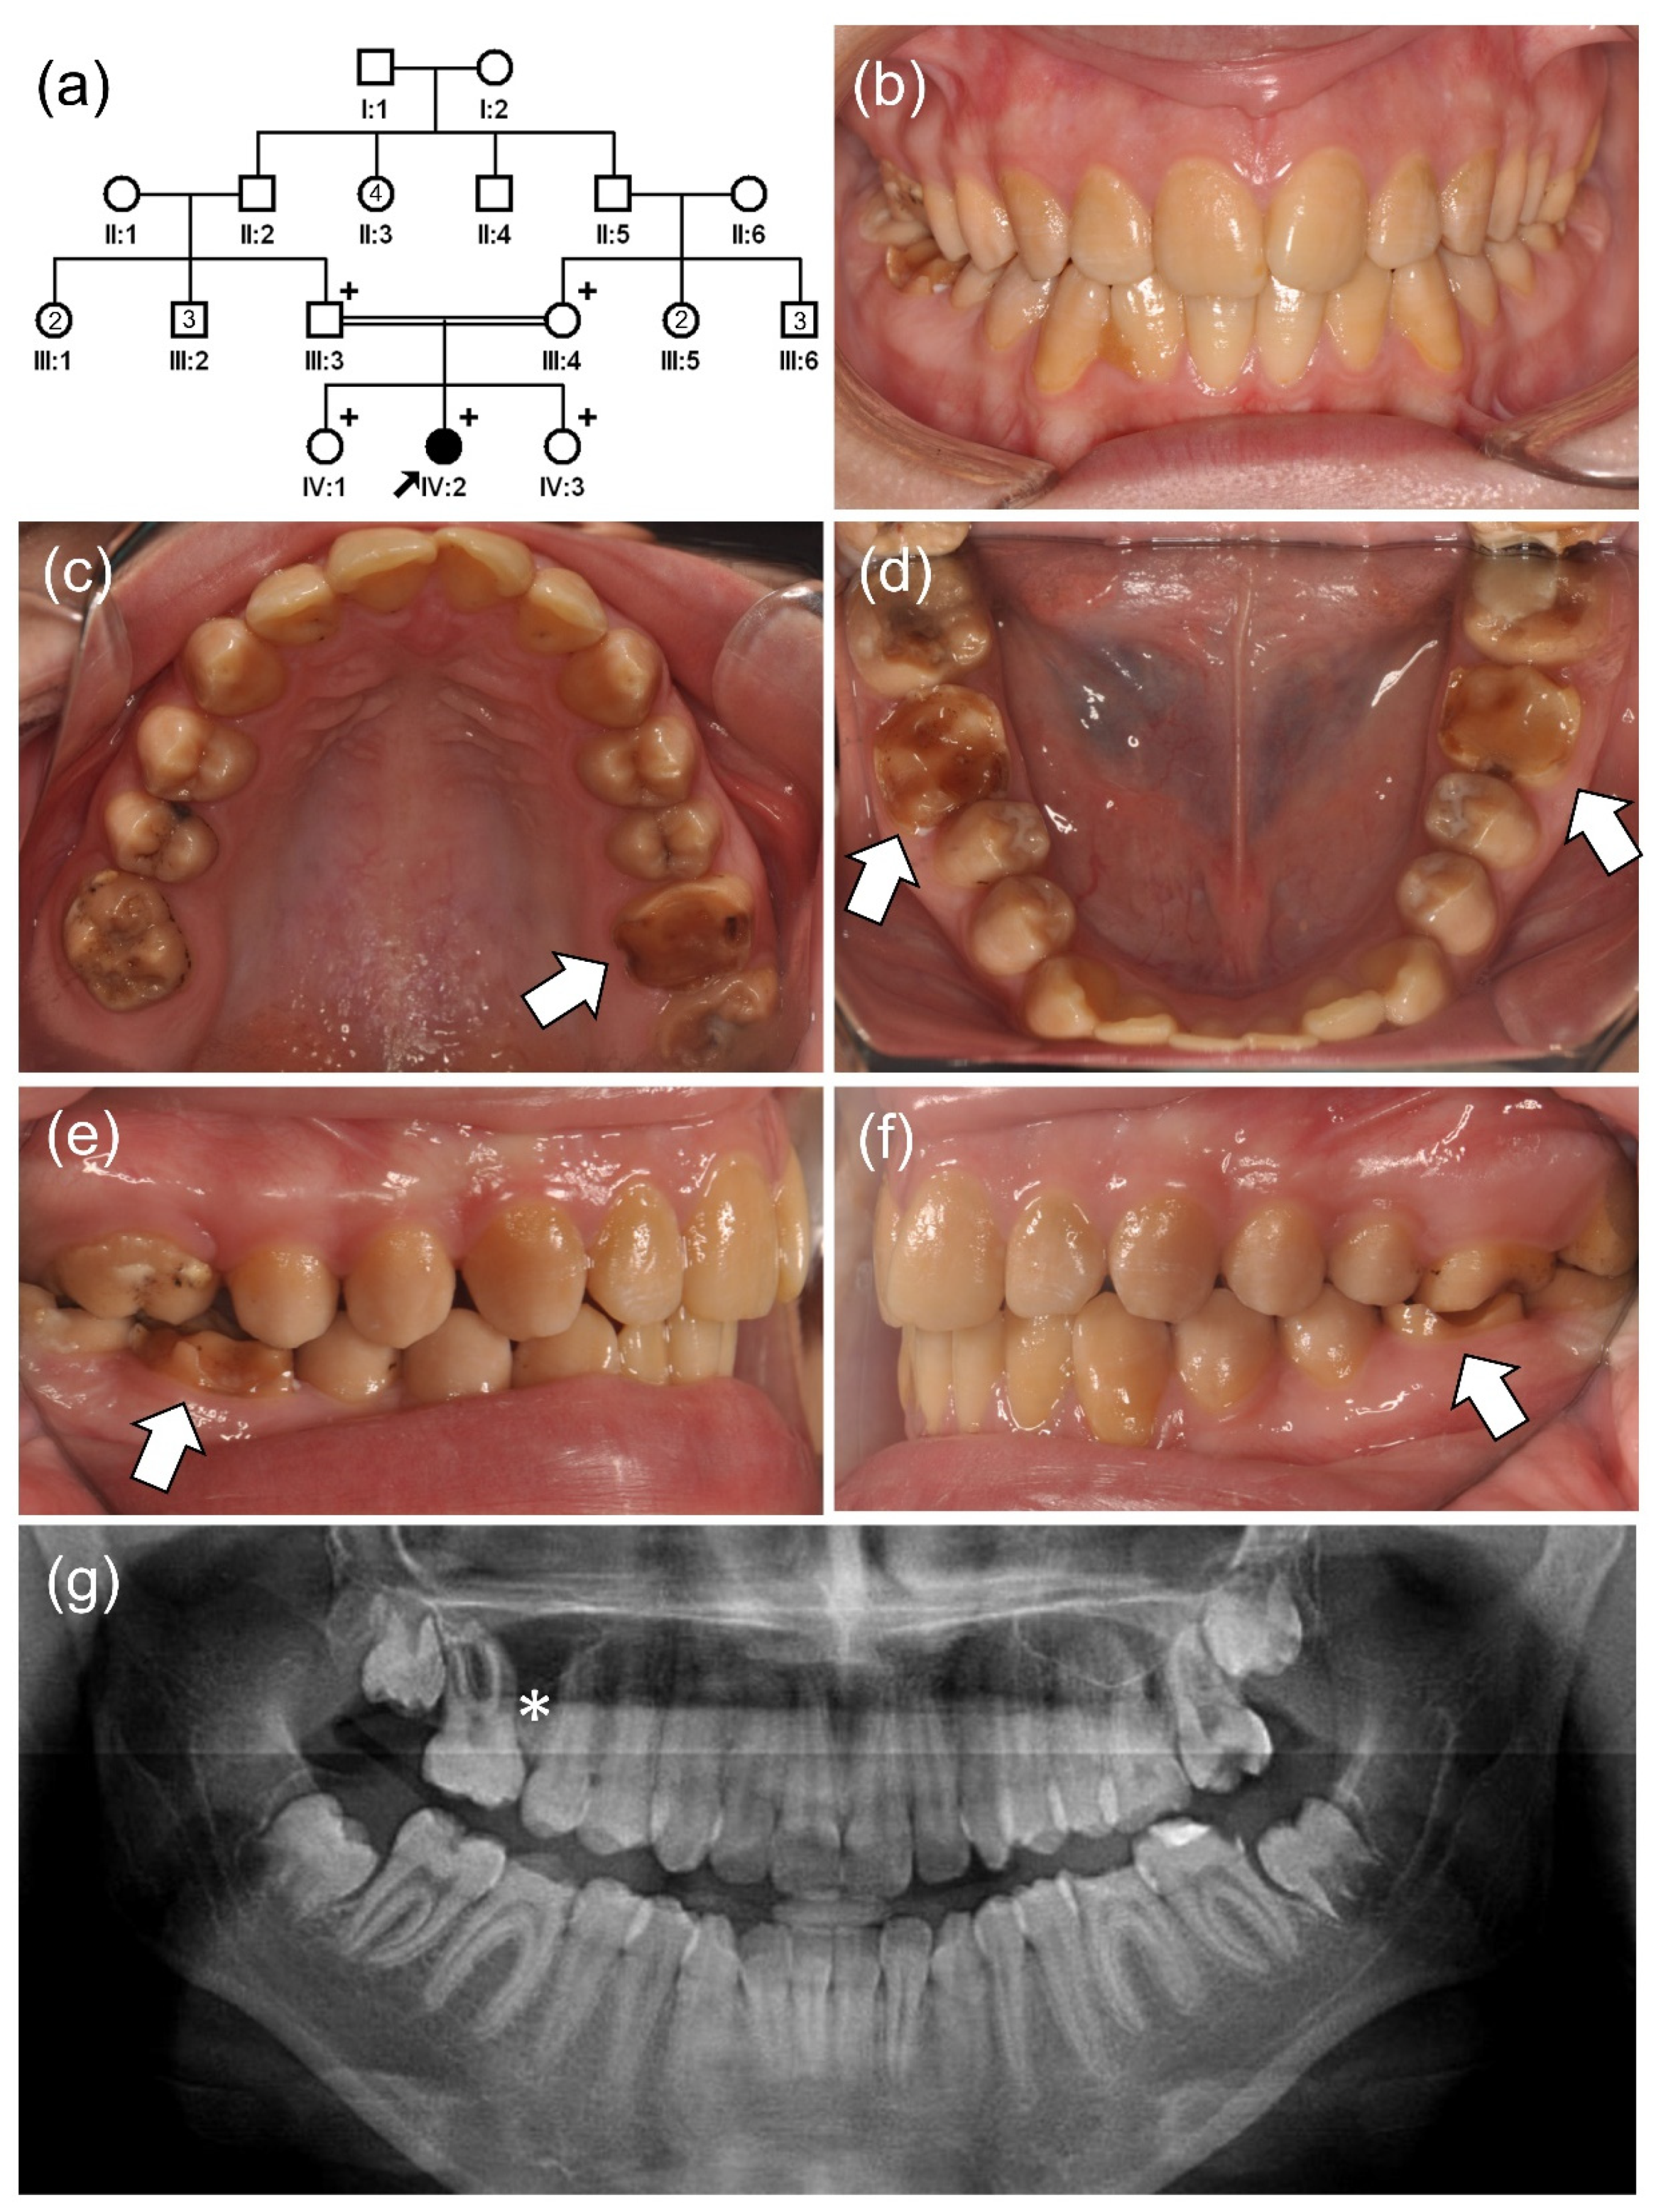

3.2. Family 4